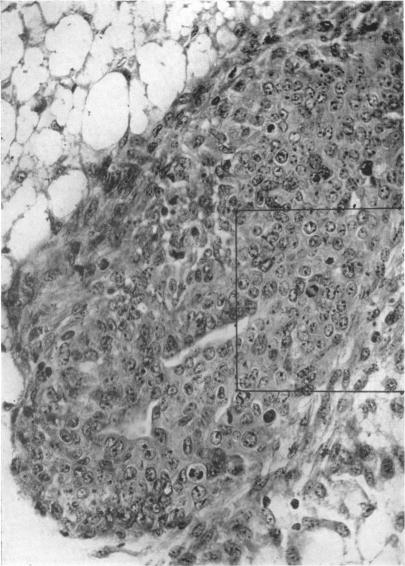

The application of physiological principles to hormone-dependent breast cancer.

Ann R Coll Surg Engl. 1958 Feb;22(2):73-106.